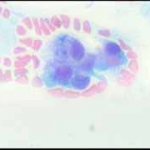

Ατυπα κύτταρα ενδοτραχήλου, άμεση χρώση με bleu de methylen 0,25% μεγεθ. 10Χ40. Αδενοκαρκίνωμα ενδοτραχήλου - ενδομητρίου